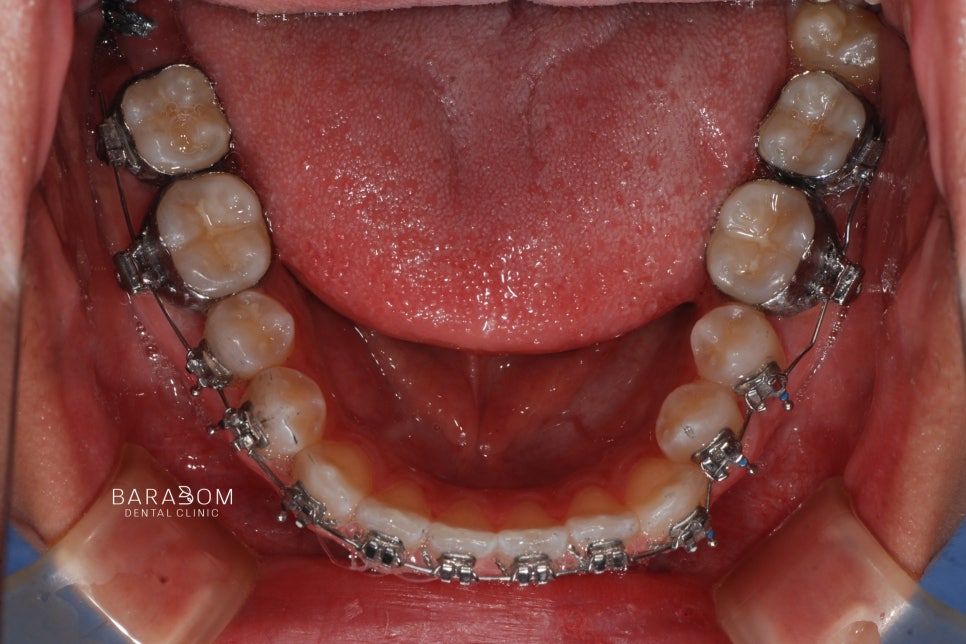

아랫 치열을 당기는 힘을

조절하기 위해서 스프링을 사용합니다.

✔동시에 어금니는 정출 즉,

위로 올라오도록 유도하고

아래턱은 시계방향으로 회전하여

전치부의 정상적인 맞물림을 위해

윗쪽 앞니의 정출을 유도합니다.

더불어 미니 임플란트를 활용하여

아래 치열의 후방 이동을

더욱 확실하게 유도합니다.

이와 더불어 3급 부정교합임에도 2급 고무줄을 활용하여 긍정적인 변화를 유도합니다.

고무줄의 탄성을 이용해

적절한 위치로 배열을 도모하는

방법을 사용하는 것입니다.

윗니는 뒤로 보내면서

아래 치아를 앞으로 당기며

교합을 조절하는 과정에서

탄성을 활용합니다.

어떤 위치에 걸어주느냐에 따라

유도하는 방향이 달라지는데요,

✅대개 2급 환자에게 시행되지만

이 경우 맞물림을 시계방향으로

회전하는 과정이 필요하여 적용하는 것입니다.